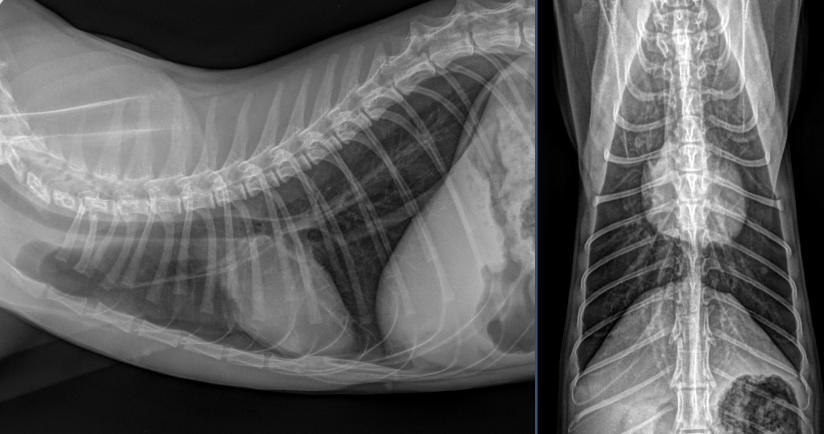

Besten Dank für die Übermittlung dieses spannenden Falles! Es liegen Röntgenbilder des Thorax und des Abdomens in 2 Ebenen vor (sinistro-dextraler Strahlengang, sowie ventro-dorsaler Strahlengang). Wesentliche Hauptbefunde sind im Bereich des muskuloskelettalen Systems, als auch im Abdomen zu vermerken.

Auffallend im Abdomenröntgen sind runde, homogene, weichteildichte Strukturen, die um die Harnblase lokalisiert sind und sich etwa auf Höhe von L5, sowie L6-7 (pinke Pfeile) befinden. Ihre Ausdehnung entspricht in etwa der Länge eines lumbalen Wirbelkörpers. Im kranialen Abdomen ist das seröse Detail zudem etwas reduziert. Im gesamten Verdauungstrakt findet sich weichteildichtes, teils auch mineraldichtes, granuliertes Material, begleitet von einer moderaten Menge an Luft (exemplarisch mit pinken Pfeilköpfen markiert). Freies abdominales Gas ist nicht nachweisbar und die Harnblase stellt sich intakt dar.

Trachea/Ösophagus, Mediastinum, Pulmonalgefäße, Aorta/V.cava, Pleuralraum, sowie alle abgebildeten ossären Strukturen stellen sich unauffällig dar. Die Herzsilhouhette misst im VHS 7,5 Wirbelkörper. Das Thoraxröntgen stellt sich somit unauffällig dar, ohne Hinweis auf Rippenfrakturen, Pneumothorax oder Lungenkontusionen.